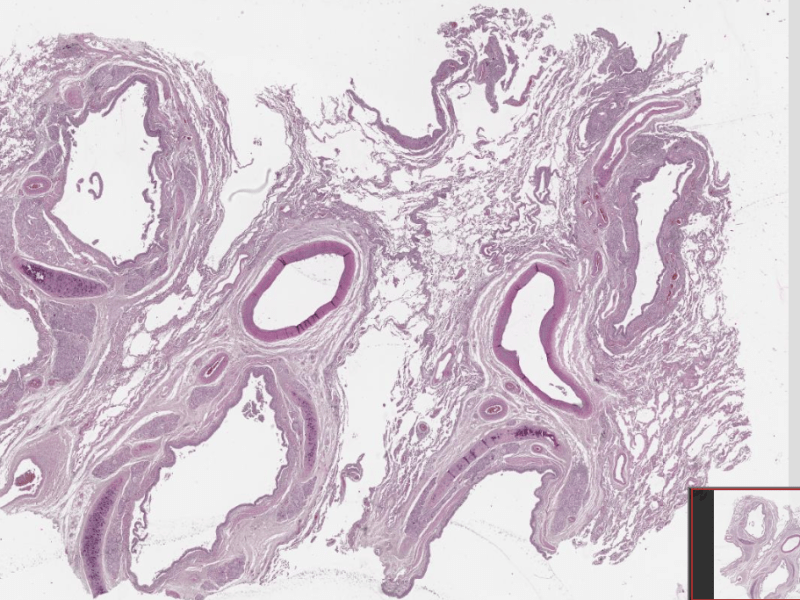

Плоскоклетъчен карцином на бронха

Виждам бял дроб. Отляво е разположен бронх (хиалинен хрущял ), участък с метаплазия, преминаване на едноредния цилиндричния респираторен епител в многослоен плосък и дисплазия. Инфилтрация в стената на бронха от гнезда и повлекла от атипични плоскоепителни клетки, зони на некроза, кератин и стромна реакция. Въпроси? Макроскопски форми на карцинома на белият дроб? – голям прехилусен…